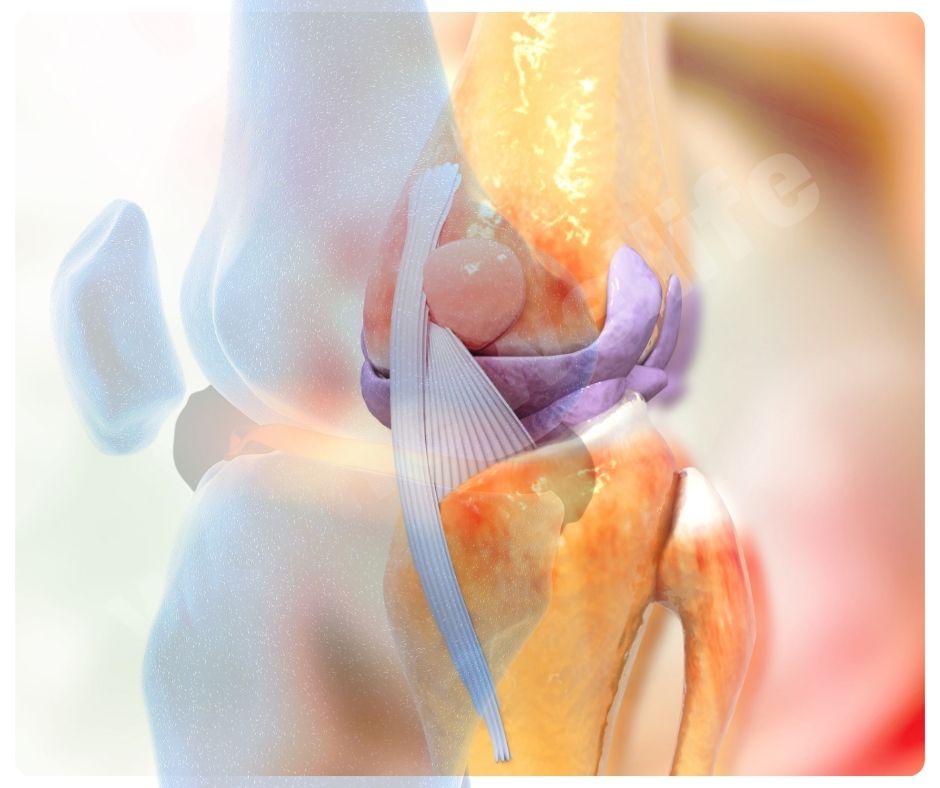

관절 기능 개선

콘드로이친 효능은 관절의 움직임을 부드럽게 하고, 전반적인 관절 기능을 개선하는 데도 효과적입니다. 이는 관절염 환자뿐만 아니라 관절 건강을 유지하고 싶은 모든 사람들에게 유익합니다.

- 관절 윤활: 관절액의 생산을 촉진해 관절의 윤활을 개선하는 효능이 있습니다.

- 관절 유연성 향상: 관절의 유연성을 높여 활동성을 증가시킵니다.

연골 재생 촉진

최근 연구에 따르면 콘드로이친 효능은 연골 세포의 생성을 촉진하고, 연골 조직의 회복을 돕는 효능이 있어요. 2023년에 발표된 한 연구에서는 콘드로이친이 연골 세포의 대사 활동을 증가시키고, 연골 조직의 손상을 줄이는 데 효과적이라는 결과를 보여주었습니다.